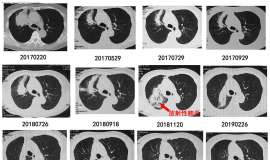

母亲肺腺癌,吃伏美替尼三个月,第一个月ct显示只小了一点点点,母亲感觉还可以,昨天吃药整三个月,但是肺部肿瘤变大,脑部也变大?是耐药了,还是控制不住,求方法,三个月太快了吧。 ...